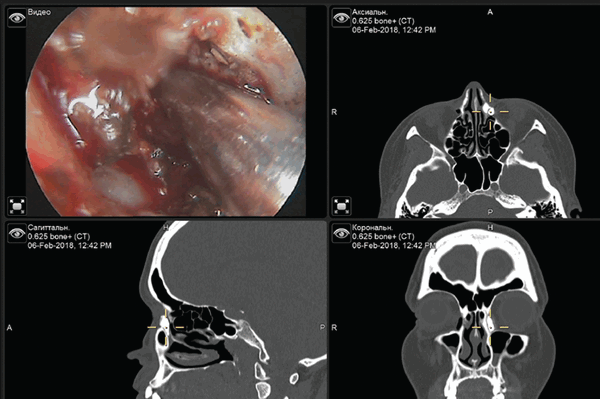

Оперативное вмешательство (ревизионная ЭЭЛДЦРС в 2018 г.) выполняли в условиях клиники оториноларингологии под общим наркозом, под контролем навигационной системы и при помощи полупроводникового лазера с длиной волны 970 нм в контактном непрерывном режиме (рис. 2).

Рубцовую ткань иссекали в проекции костного окна. Далее при помощи бора удаляли остатки костного массива. На заключительном этапе через верхнюю и нижнюю слёзные точки постановили биканаликулярный силиконовый стент с последующей фиксацией его концов узлами в полости носа. На каждом этапе нахождение инструмента относительно структур полости носа контролировали при помощи навигационной станции (рис. 3).

Рис. 3. Изображение с навигационной станции, показывающее рентгенологическую и эндоскопическую картину полости носа и слезоотводящих путей

Fig. 3. The image from navigation station showing X-ray and endoscopic view of nasal cavity and lacrimal pathways

Навигационное оборудование использовали для точного определения структур полости носа и слёзных путей в условиях изменённой анатомии, что способствовало точному планированию и безопасному проведение эндоскопического вмешательства.